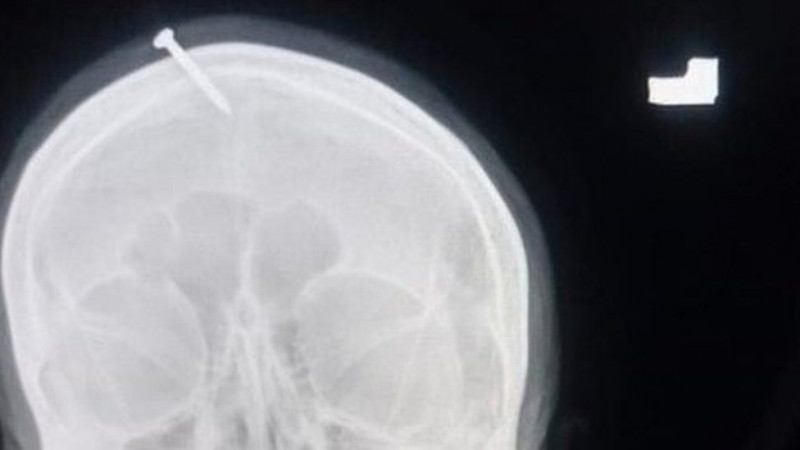

Un vraci i-a înfipt un cui în cap unui femei, spunând că în acest fel va naște un băiat

cui înfipt în cap

În Pakistan a fost pornită o anchetă după ce un vindecător i-a înfipt un cui în capul unei femei care era însărcinată. Acesta i-ar fi promis că dacă face acest lucru, femeia va naşte un băiat. Femeia a ajuns la un spital din Peshawar după ce a încercat singură să extragă cuiul cu un clește. La început, aceasta le-a spus medicilor că ea și-a înfipt cuiul, dar mai târziu a recunoscut că un vraci, care i-a promis că astfel ea va naște un băiețel.

Poliția a început cercetările după ce imaginile au apărut pe internet. Dr Haider Khan a spus că femeia era „pe deplin conștientă, dar avea dureri mari” când a sosit în căutarea tratamentului.

Poliția a vorbit cu medicii încercând să-i dea de urmă femeii, care a părăsit spitalul după ce i-a fost scos cuiul din cap, în speranța că ea îi poate ajuta să identifice bărbatul. „În curând, vom pune mâna pe vrăjitor”, a spus şeful poliţiei din Peshawar, Abbas Ahsan. De asemenea, Ahsan a adăugat că ofițerii încearcă să stabilească și care este motivul pentru care medicii nu au raportat incidentul.